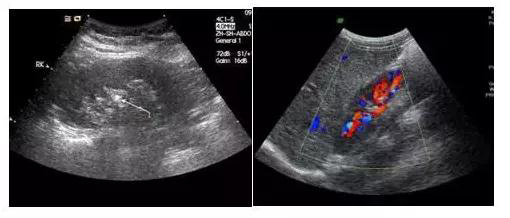

它們的區(qū)別是黑白超用灰度調(diào)制顯示聲束掃描人體切面的聲像圖;彩超則是在黑白超的基礎(chǔ)上,增加了血流信號(hào)的處理,一般用紅、藍(lán)、綠三種基本顏色,呈現(xiàn)出檢查區(qū)域的血管分布、血流方向、血流速度等。

圖片

黑白超                            彩超